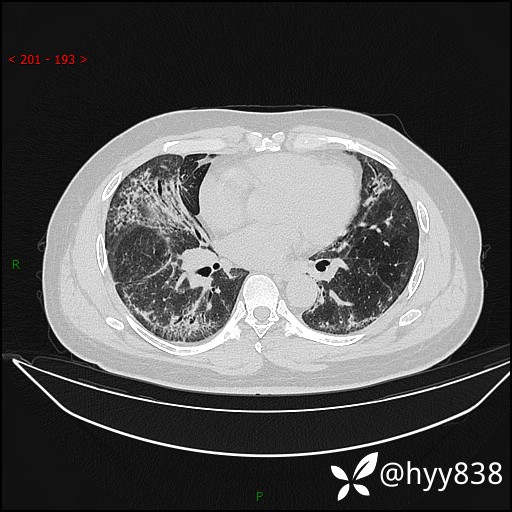

辅助检查:CT

临床诊断:间质性肺炎

第二次CT(7天后)